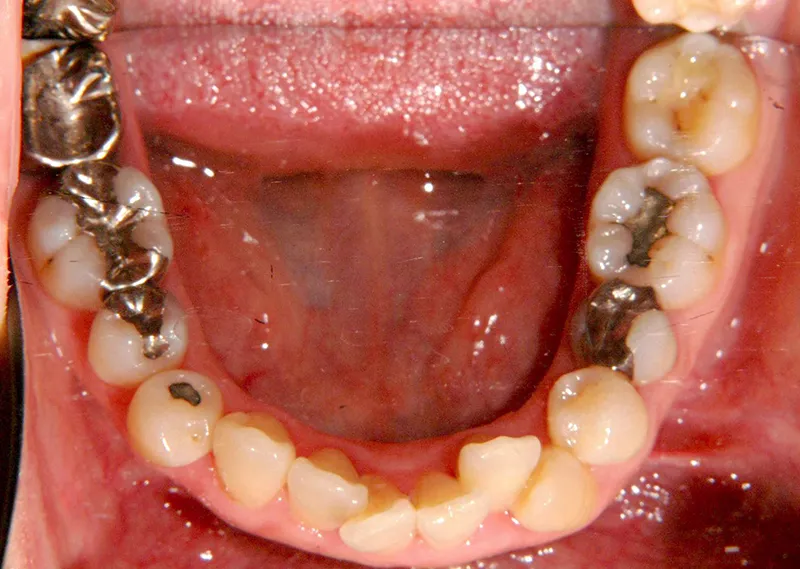

初診時年齢 40歳以上 (女性) 主訴 上下のがたがた・噛み合わない

診断名 叢生 装置名

特徴 ゆがんで生えている

状態 ガタガタ・でこぼこに生えている(叢生)

八重歯(叢生)

上下のがたがたと噛み合わない事を主訴に来院されました。

歯は抜かずに矯正治療しました。

初診